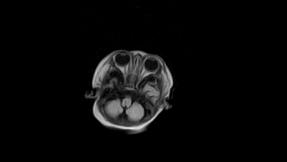

标题: PED3413:患儿女6天体检

缺血缺氧性脑病

6天为新生儿,髓鞘发育正常;左侧颞顶叶蛛网膜下腔增宽,请结合临床。

1。缺血缺氧性脑病2。左侧颞顶叶外部性脑积水,可观察

半卵圆中心上方层上可见对和乐大脑皮质t1高信号,考虑有hie可能,不知有何症状,建议加做dwi及复查

符合缺氧缺血性脑病影像表现。